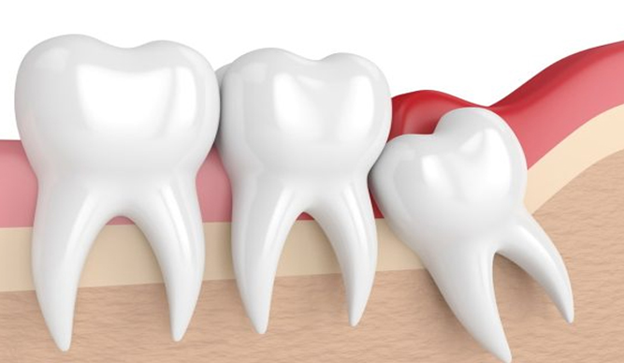

3. Ảnh hưởng nghiêm trọng đến răng số 7

- Răng khôn mọc lệch hoặc mọc ngầm có thể đâm ngang, chèn ép răng số 7.

- Hậu quả: ê buốt, lung lay, tiêu xương quanh răng số 7.

- Trường hợp nặng có thể dẫn đến mất răng số 7 vĩnh viễn nếu không can thiệp kịp thời.